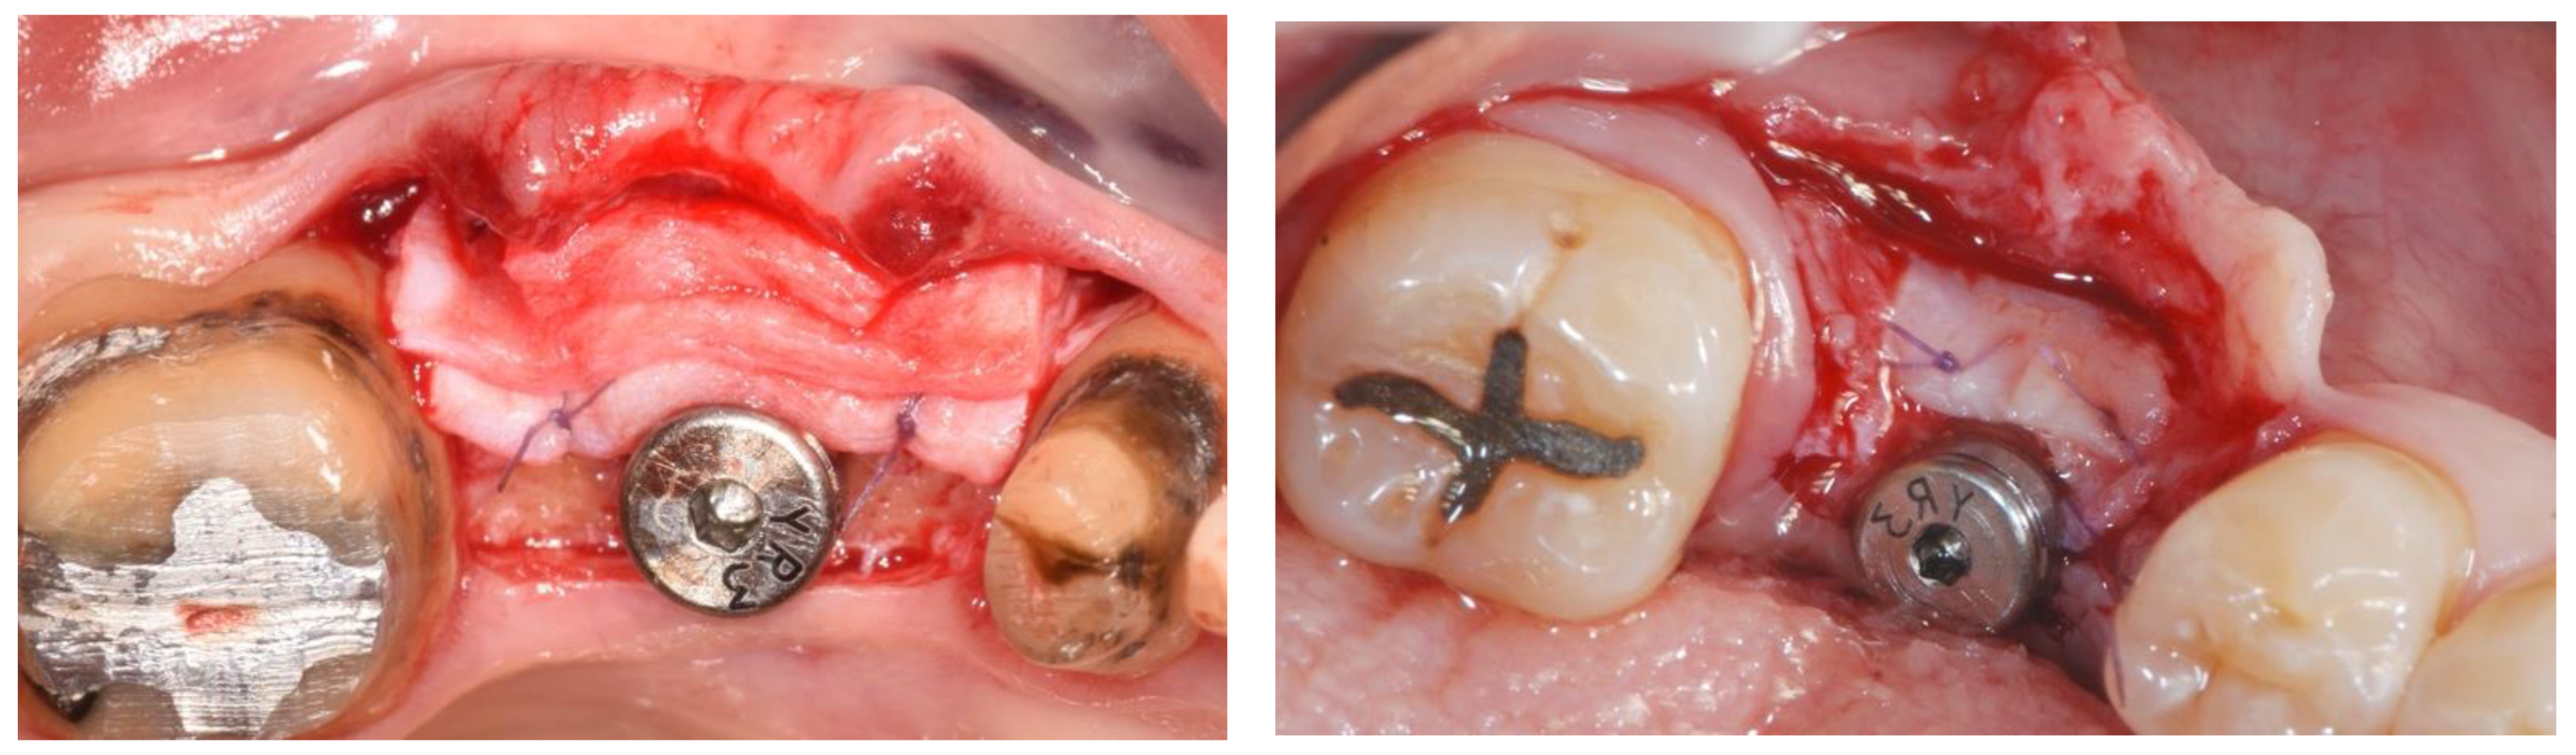

| Papi et al. [27] | 12 patients | Prospective cohort study | 12 months | N R | PDXCM: 1.25 |

| Zafiropoulos et al. [38] | 27 patients | Prospective, randomized examiner-blinded controlled clinical study | 6 months | N R | PDXCM: 1.06 |

| Stefanini et al. [39] | 10 patients | Case series | 12 months | PDXCM 0.65 ± 0.41 | PDXCM: 1.2 ± 0.18 |

| Papi and Pompa 12 [40] | 12 patients | Prospective pilot cohort study | 12 months | PDXCM: 4.32 | N R |

| Schmitt et al. [41] | 14 patients | Controlled clinical trial | 6 months | N R | PDXCM: 0.30 ± 0.16 |

| Verardi et al. [42] | 24 patients 24 implants | Prospective study | 6 months | PDXCM 1.33 ± 0.71 | N R |